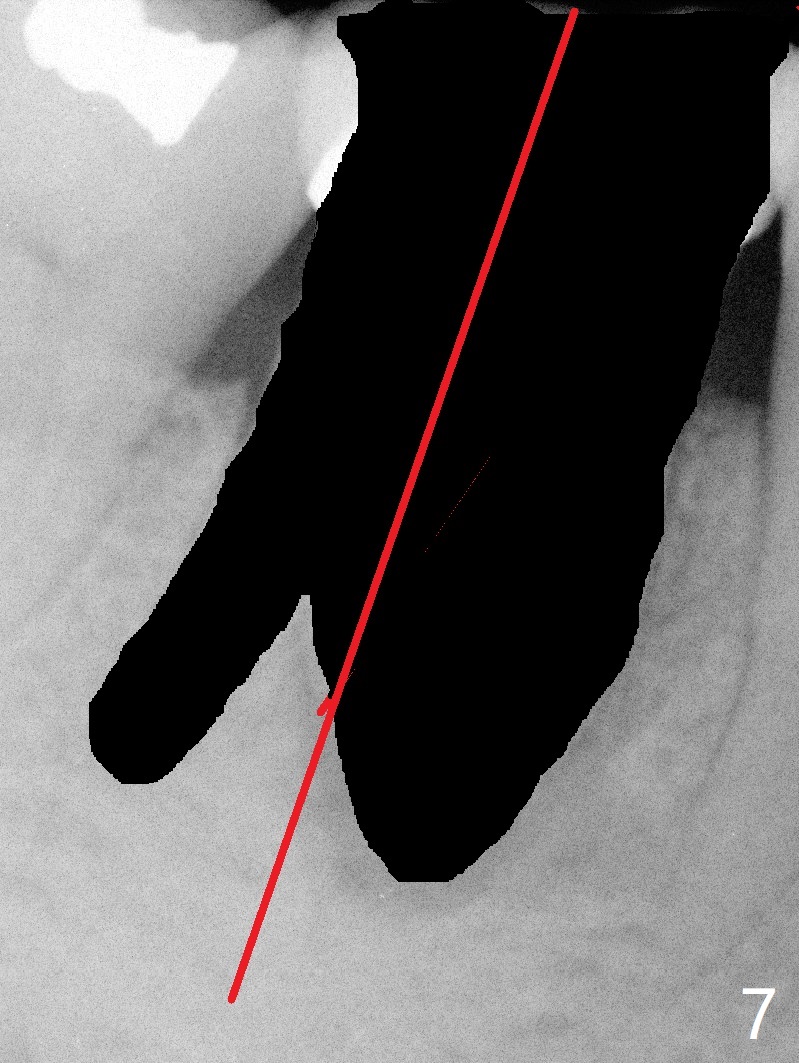

A 55-year-old woman has severe bone loss (Fig.1 with buccal and lingual fistulae) around the mesial (M in Fig.2) and distolingual (DL) roots. If there is a septum after extraction (Fig.3 S), osteotomy will be established in the septum to enhance primary stability (Fig.4). When the septum cannot be saved (Fig.5), osteotomy is to be initiated in the septal slope oblique (Fig.6 <). The osteotomy will be straightened once an entry is made (Fig.7). The initial osteotomy is slightly distal, since as osteotomy increases (Fig.8 blue), it tends to shift mesial (arrow). In addition, the apex of the 2nd bicuspid tilts distal (yellow dashed line). Depth of osteotomy is 20 mm (crest, Fig.9) or 18 mm (septum) so that 8 mm of the native bone can be obtained with 3 mm clearance from the Inferior Alveolar Canal (red dashed line). PRFx2 is required (seems not done).